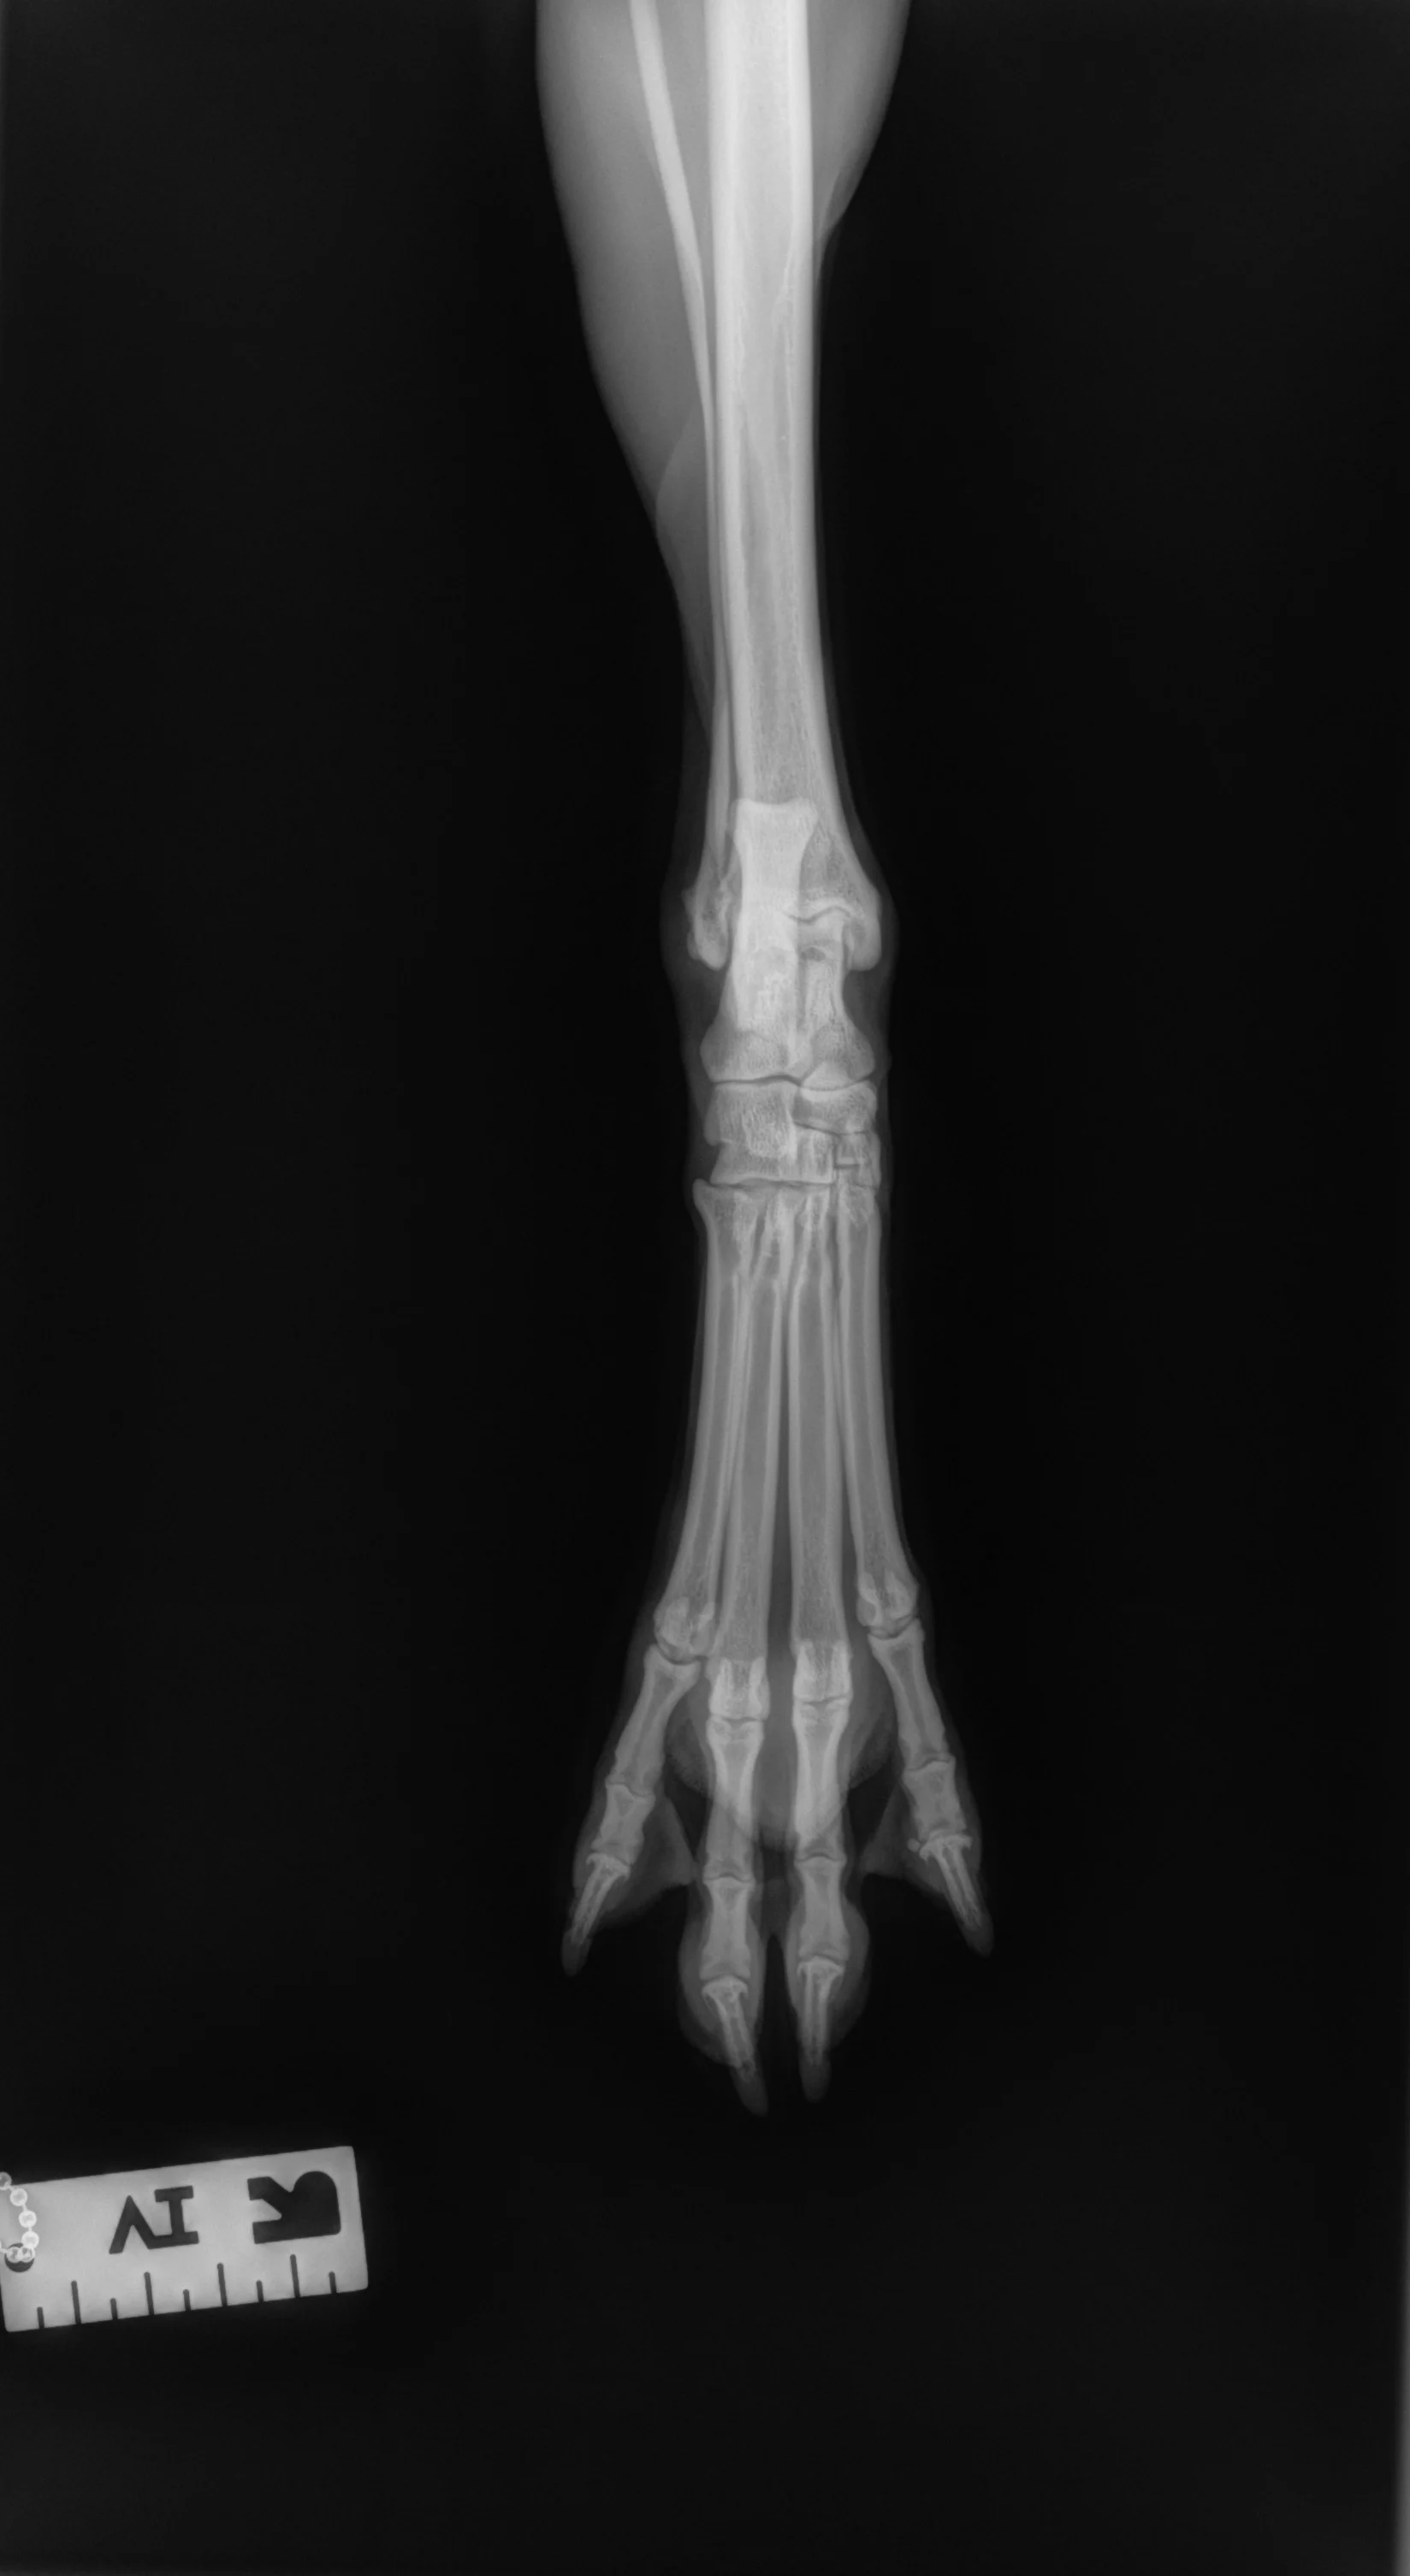

Author Insight

All digits should be separated and clearly visible. The bony edges of the metacarpal bones should be parallel to each other (arrows), and all phalanges (P1 [A], P2 [B], P3 and nail [C]) should be included.